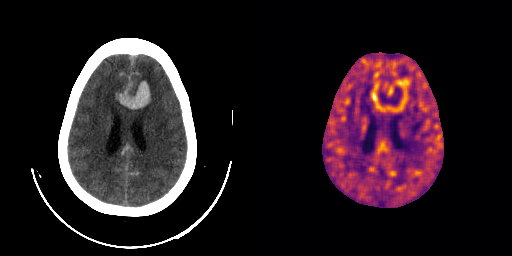

fig:qualitative_ich

ICH

healthy

We show some slices with examples of ICH in \figurereffig:qualitative_ich as well as surface renderings of scans of subjects with cranial fractures in \figurereffig:qualitative_fractures. (As a reference we also included the same examples for the AE in Appendix D in \figurereffig:qualitative_ich_ae.) It is noticeable that the reconstruction error is high where there is an anomaly. The reconstruction error generally seems to continuously depend on the amount of the patch that is anomalous, as the error maps generally seem to be rather smooth.

The performance for the models used for \figurereffig:qualitative_ich and LABEL:fig:qualitative_fractures are shown in \figurereffig:roc_performance. We observe see that the detection of fractures is the more challenging task for our method than the detection of ICH. This might be due to the smaller number of scans available to evaluate it on (see Appendix B). To put these results in context we provided a table with the inter rater agreement on these tasks in Appendix B: The performance in terms of AUROC is around lower than the average raters.